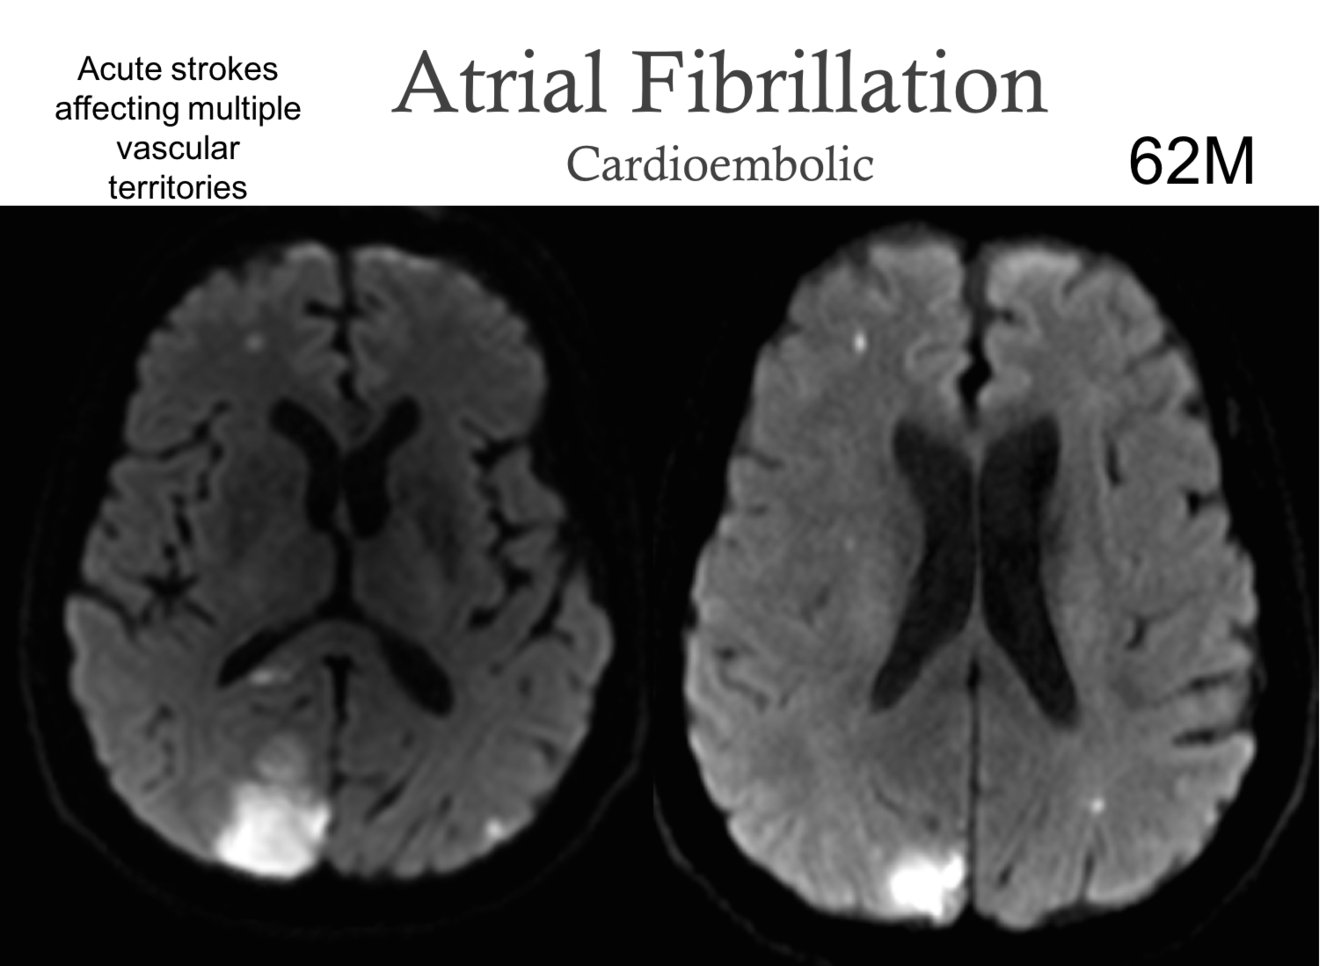

What are the signs of a Atrial fibrilation (cardioembolism)?

Acute stroke affecting multiple vascular territories